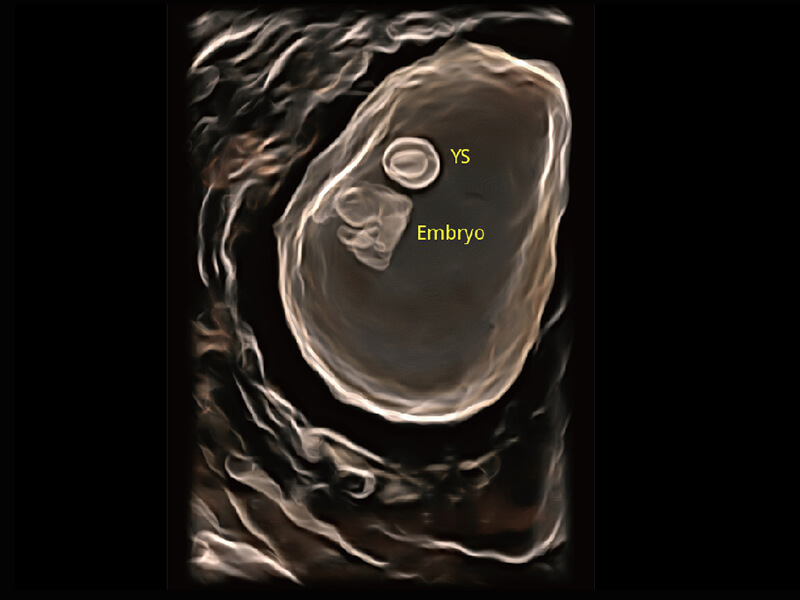

S60探头工艺,从前端信号处理每一个环节采集无损声学数据,真实还原组织原貌,再现解剖细节。

超宽频带技术,为容积成像带来优质的二维图像基础,为您呈现丰富的结构细节,栩栩如生地展示宝宝的宫内形态以及各种组织的立体结构。